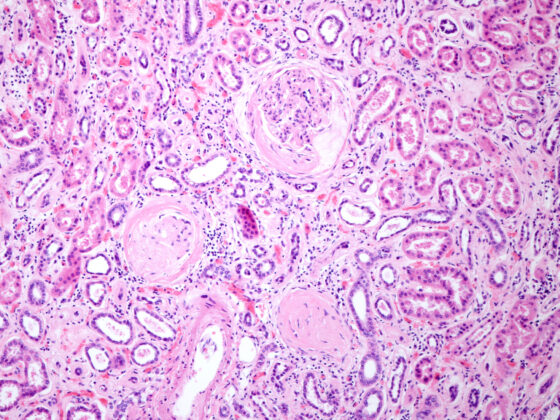

Die bariatrische Chirurgie kann kardiometabolische Funktionen wie Blutdruck, Cholesterin, Glukose und HbA1c deutlich verbessern. Forscher stellten fest, dass bei 30 bis 50% der Menschen, die sich einer bariatrischen Operation unterzogen, Diabetes, Bluthochdruck und Dyslipidämie verschwanden. Die bariatrische Chirurgie kann zu erheblichen kardiometabolischen Verbesserungen führen, insbesondere bei jüngeren, weiblichen oder weissen Personen und bei Personen ohne Begleiterkrankungen, so eine Studie, die im Journal of the Endocrine Society veröffentlicht wurde.